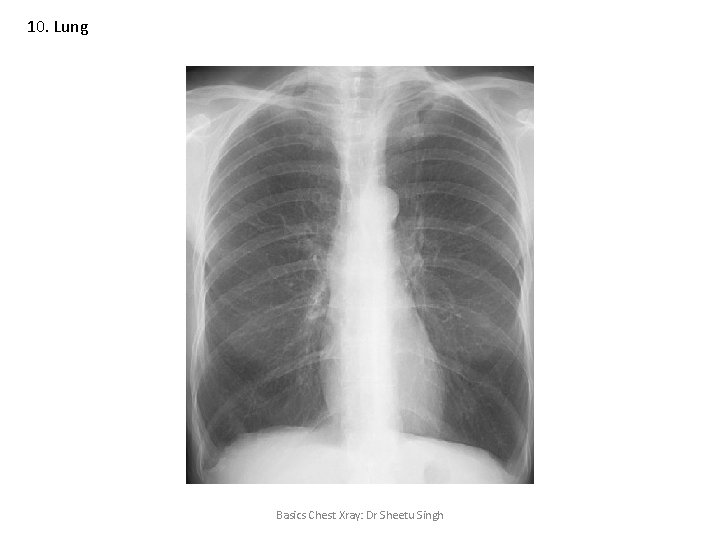

10. Lung Basics Chest Xray: Dr Sheetu Singh